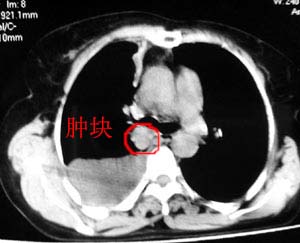

图像不是太好,但可以见到下列恶性征象:

1 单侧肺门增大

2 纵隔侧胸膜明显增厚

3 肋胸膜结节影

结合纵隔略宽、单侧胸水首先考虑肺癌。

以下是引用gaozhengyi在2006-4-12 7:18:00的发言:[br]图像不是太好,但可以见到下列恶性征象:[br]1 单侧肺门增大[br]2 纵隔侧胸膜明显增厚[br]3 肋胸膜结节影[br]结合纵隔略宽、单侧胸水首先考虑肺癌。

在加右腋下淋巴结肿大

考虑纵隔旁肺癌伴胸水可能。

同意9楼分析,肺癌,胸膜转移、胸水。

右侧胸膜结节状增厚伴胸腔积液及纵隔、腋窝淋巴结肿大,考虑胸膜间皮瘤可能性大;建议胸膜活检。

右侧中央型肺癌合并阻塞性肺炎及右侧胸膜转移。

右侧肺门淋巴结肿大,伴大量胸腔积液,同侧胸膜结节样增厚,有胸膜粘连,考虑肺癌.